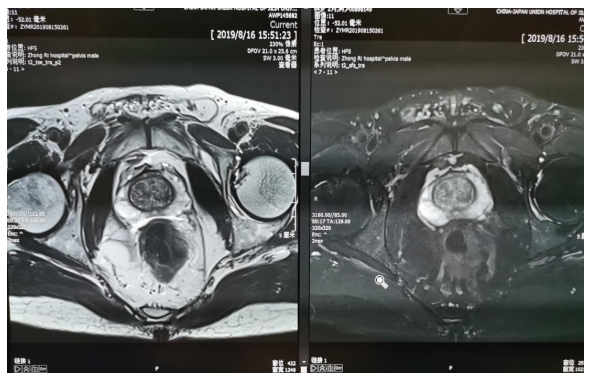

前列腺增生